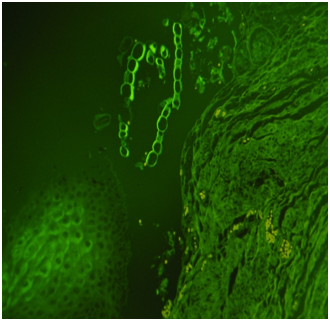

Histology: Acute emphysema was the prominent observation; edema and hemorrhages were also present.4 In 9 cases (Figures 3-6), exogenous material in the airways, comprehensive of planktonic boli in the lower branches, clearly demonstrable at polarization microscope (and possibly confirmable at SEM’s elemental analysis with EXD). Zoo- and phytoplankton have been better identified in the UV microscope. It is mandatory to differentiate the planktonic material from gastric content, regurgitated and aspirated (Figure 7 & 8).

Figures 3,4 Drowning in seawater. Images of endoalveolar zooplankton (protoconch of crustacean) (EE, 480 X, polarized light).

Figure 5 Drowning in freshwater; recovery corpse in the sea after 20 days. Endoalveolar phyto- and geoplankton (EE, 240X, polarized light).

Figure 6 Drowning in freshwater; recovery corpse after few hours. Geo- and phytoplankton in a lower bronchus (EE, 120X, polarized light).

Figure 7 Same case of Fig. 7. Fragments of food (cooked meat and tuber cells) in the main stem bronchus (EE, 240X).

Figure 8 Same case of Fig. 7. Plant material identified in the esophageal mucosal laceration (EE, 480X, UV).